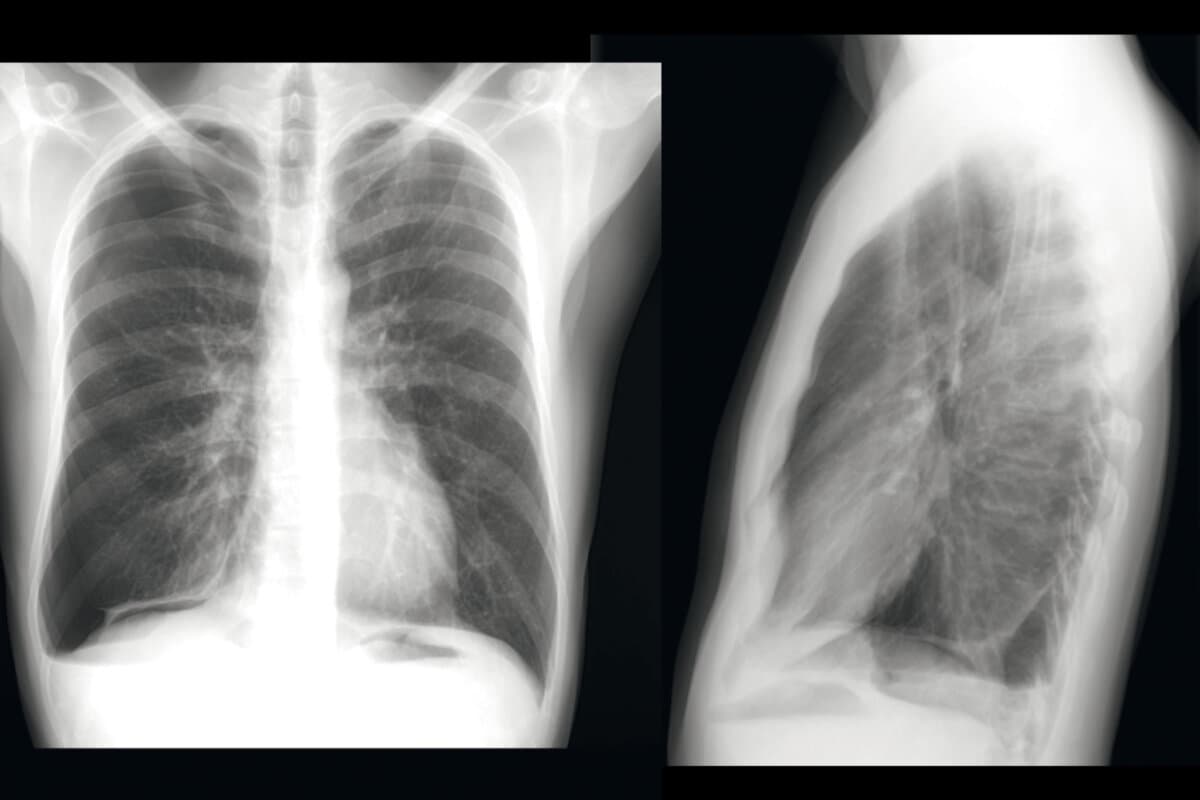

COPD 2026: Jede Exazerbation zählt

Die klassische Definition der COPD bleibt bestehen, dennoch gibt es relevante klinische Entwicklungen, berichtete Prim. ao. Univ.-Prof.in Dr.in Judith Löffler-Ragg von der Pneumologie Natters in Tirol beim Pneumo Aktuell: Adaptierte GOLD-Kriterien, neue Risikobewertungen und ein stärker integrativer Blick auf Komorbiditäten verändern Diagnostik und Therapie.